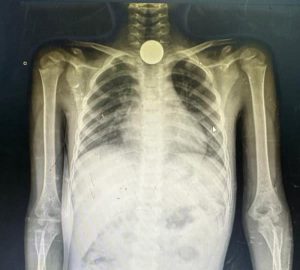

به گزارش بخش بین المللی سایت خبرمهم ، فارس نوشت: الشموسی با انتشار یک تصویر رادیوگرافی در حساب کاربری خود در شبکه اجتماعی ایکس ( توئیتر سابق) می‌گوید کودکی را در غزه معاینه کرده که یک تکه فلز را بلعیده است. او در این‌باره می‌نویسد: «کودکان غزه از شدت گرسنگی‌ سکه ، سنگ‌ریزه و باتری‌ می‌خورند… امت عربی و اسلامی مسئول هستند… این یکی از آن‌هاست که ۸ سال دارد. یک تکه فلز قورت داده و در مری او گیر کرده است.»

این پزشک عمانی همچنین در حساب کاربری خود فیلمی از داخل اتاق عمل منتشر کرده که در‌حال بیرون آوردن یک باتری از روده‌های یک کودک فلسطینی دیده می‌شود و کادر پزشکی نیز بعد از موفقیت‌آمیز بودن عمل برای او دست می‌زنند. الشموسی می‌گوید: «از شدت گرسنگی، کمبود کمک‌ها و به این دلیل که کشورهای اطرف پشتشان را خالی کرده‌اند، کودکان باتری می‌بلعند با این گمان که شکلات است.»